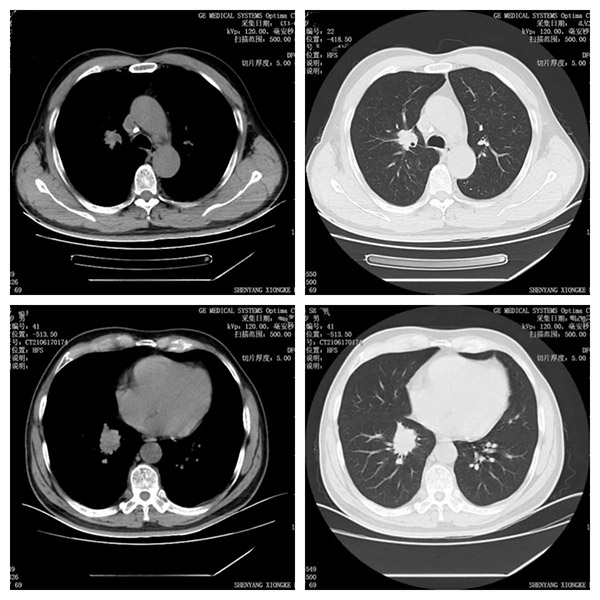

术前CT

前段时间许大爷出现了咳痰带鲜红色血,家属马上带许大爷前往医院做了肺CT检查,不幸的是许大爷右肺上叶和下叶都出现了占位性病变,家属对老人的病情非常的担心,家属在多方询问并在朋友的介绍下找到沈阳市第十人民医院介入科张申众主任,张申众主任通过详细了解患者病情后,向患者家属讲解首先要先确定右肺上下叶病灶是原发肺癌还是肠癌转移的,建议患者现行气管镜取病理明确诊断,患者家属经过考虑后决定行气管镜检查并取病理,结果令家属非常失望,病理提示腺癌,倾向于肠道转移。病理出来后张申众主任为患者制定了支气管动脉灌注化疗联合载药栓塞精准治疗的方案并向患者家属详细介绍了方案的优越性,患者家属详细了解方案后非常认可该方案。